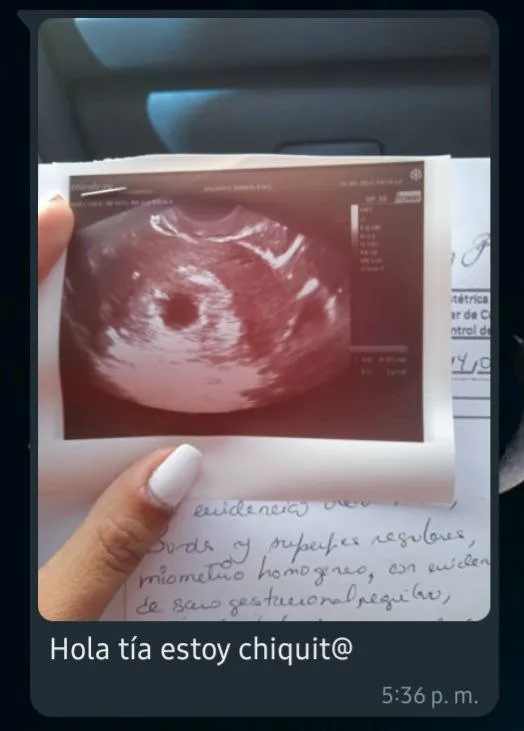

Todo esto sucedió hace un tiempo, a mediados de marzo para ser más específica, cuando mi pareja y yo recibimos cada uno un mensaje de WhatsApp de mi cuñada con la foto de una ecografía acompañada de la inscripción “Hola tía estoy chiquit@”, apenas vimos eso ambos quedamos sorprendidos y con la boca abierta, es decir, no nos esperábamos eso porque fue algo que nunca imaginamos, pues, nunca se le escuchó alguna vez hablando sobre hijos en el futuro o cosas así, pero supongo que a veces la vida nos sorprende ¿no? Como sea, eso nos alegró mucho, porque ambos tendremos nuestro primer sobrino y llegará este año, por lo que despediremos el 2023 con un nuevo miembro en la familia y el Niño Jesús visitará nuestros hogares en navidad.

All this happened a while ago, in mid-March to be more specific, when my partner and I each received a WhatsApp message from my sister-in-law with a photo of an ultrasound accompanied by the inscription "Hello aunt, I'm little @", barely we saw that we were both surprised and with our mouths open, that is, we did not expect that because it was something we never imagined, well, he was never heard talking about children in the future or things like that, but I suppose that sometimes life surprises us right? Anyway, that made us very happy, because we will both have our first nephew and he will arrive this year, so we will say goodbye to 2023 with a new member of the family and the Child Jesus will visit our homes at Christmas.